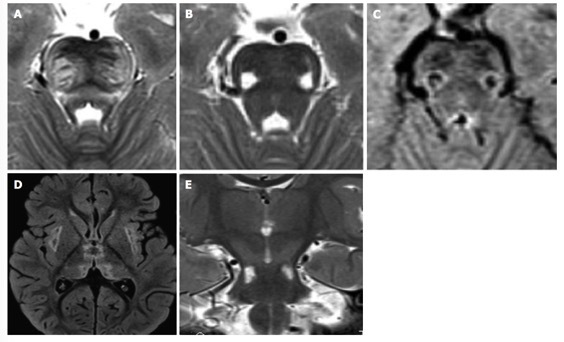

24.多系统萎缩:多系统萎缩常见于 >65 岁的患者,主要症状表现为帕金森症及神经功能障碍,目前主要分为 2 类,MSA-p 及 MSA-c 型。影像学表现:十字面包征(Hot cross bun)简称十字征。常见于 MSA-c 型,但并非特异性,还可见于 SCA2、SCA3。 其它影像学表现:中小脑角及小脑白质 T2WI 高信号征。